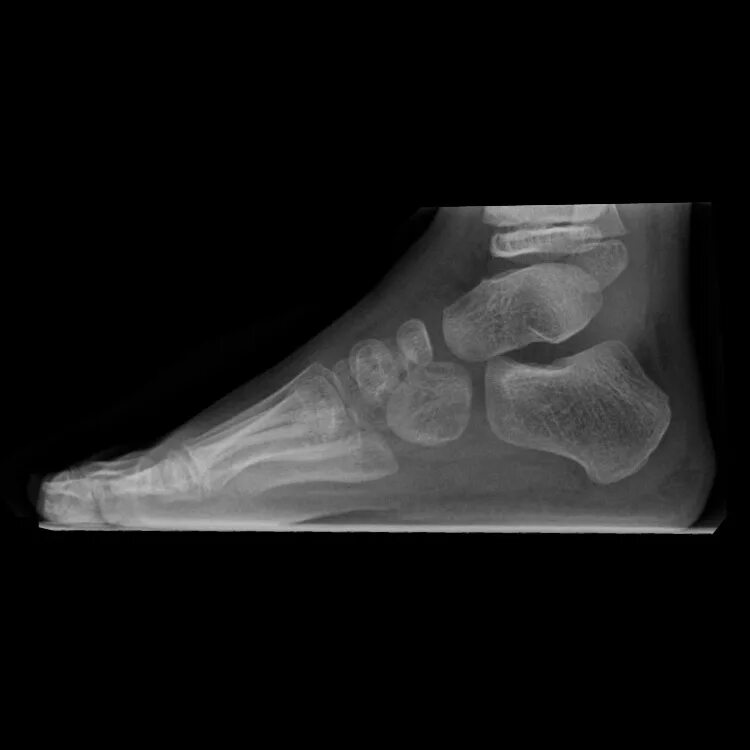

Пяточная остеотомия